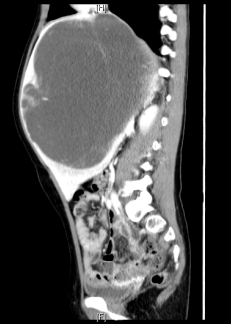

术前增强CT可见右肝巨大占位,约15x13x17cm,左肝推移,下腔静脉肝内段和中肝静脉受压,右肝静脉显示不清。